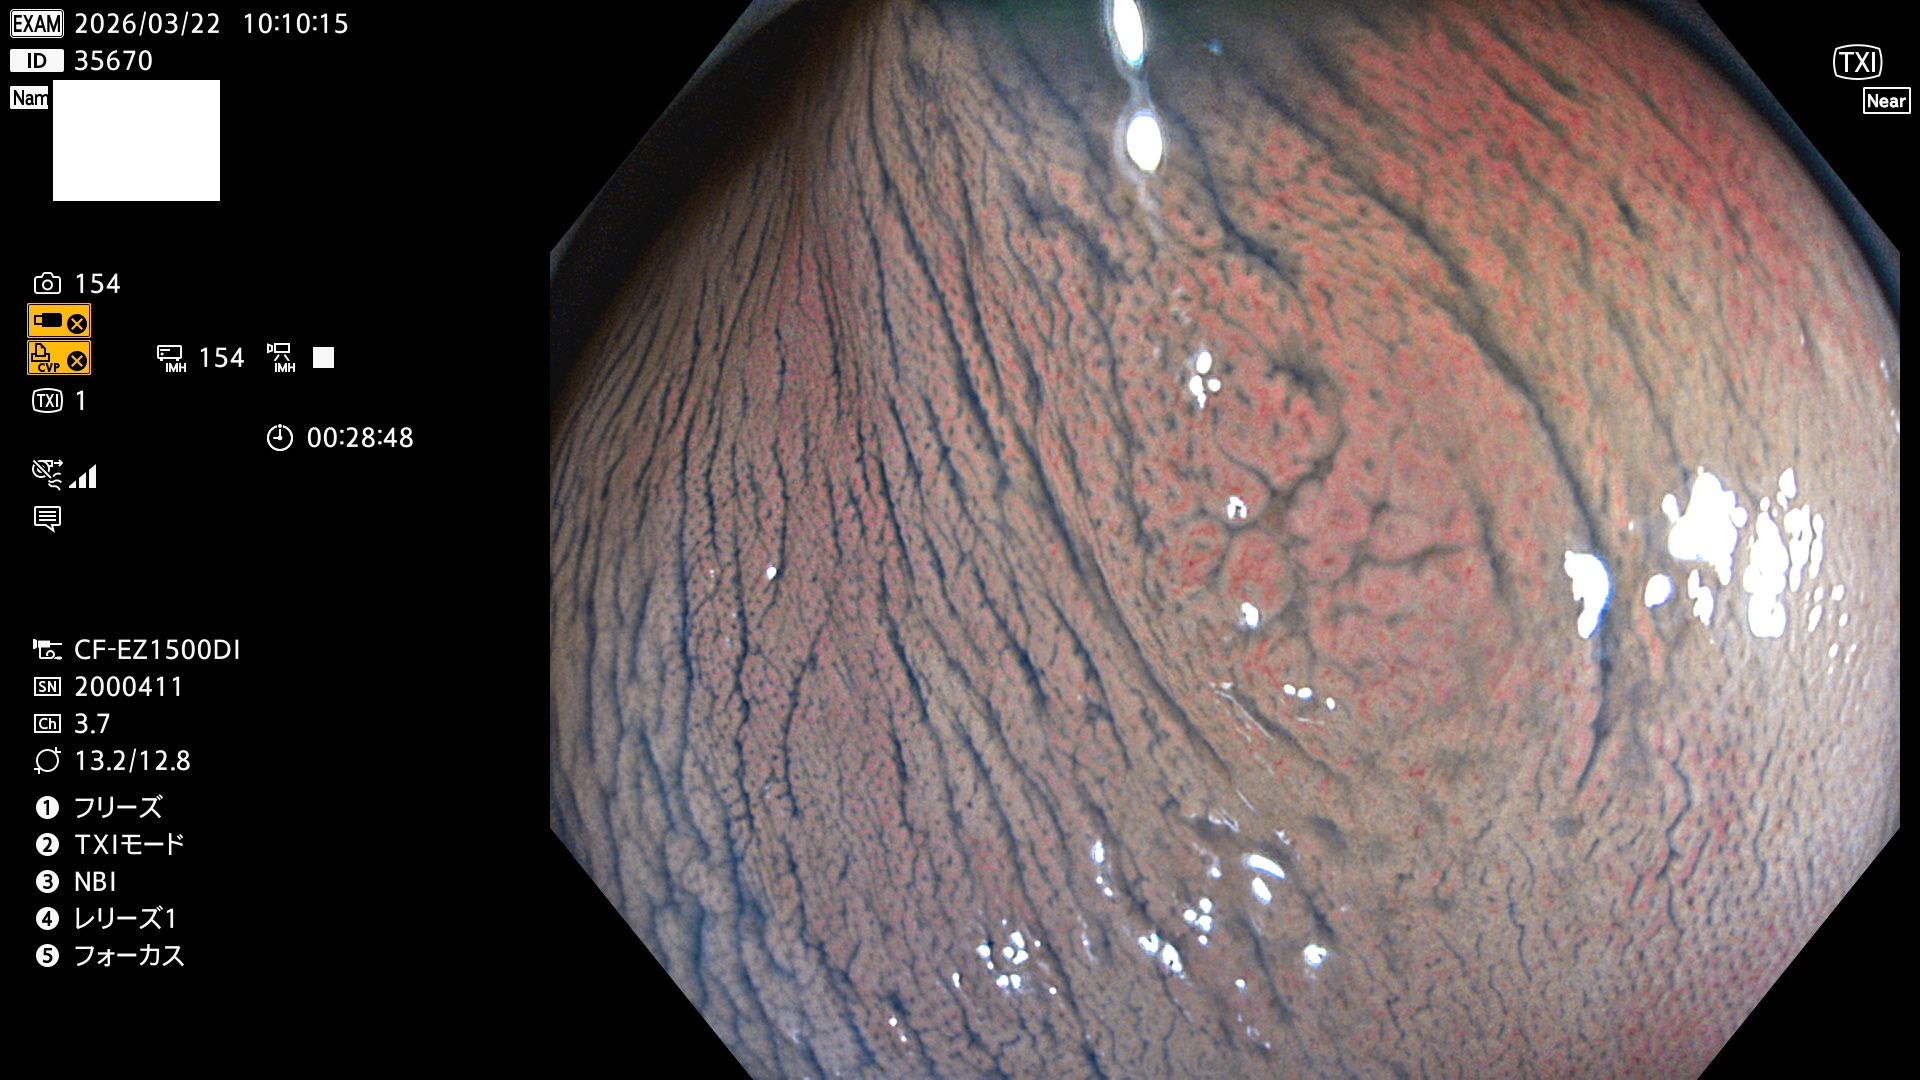

完全に平坦な物をUb、陥凹している物をUcと呼びます。Ubは認識が困難で、Ucはびらん(炎症)と紛らわしいために見落とされやすく、「内視鏡後・大腸癌」の原因になります。

毎週の検査(木・金・土・日)に発見されたUbとUc型・腺腫を、その週の日曜の夜にUPし1週間、提示します。

2026年3月19日〜3月22日の4日間(40件)4個 (Uc_ADR=4個/40人=10%)